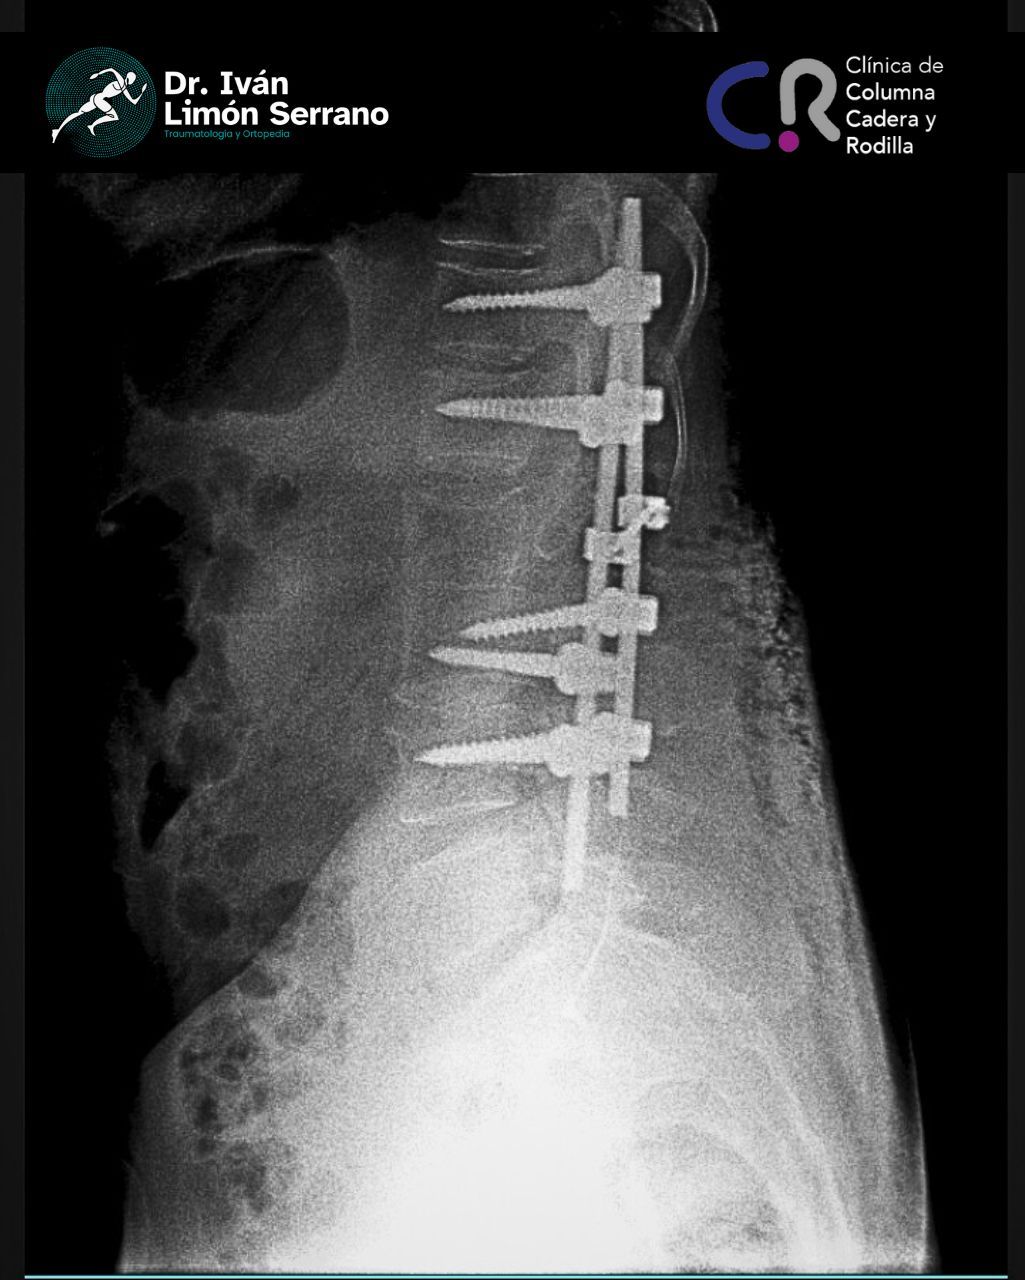

• Cirugía de columna

• Cirugía columna